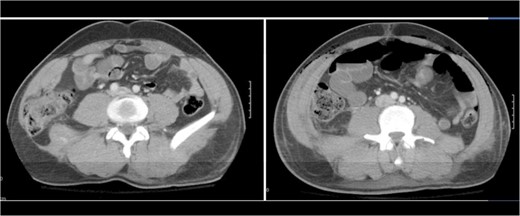

A 43-year-old male patient presented with a right-sided traumatic lumbar hernia after a blunt mechanism. The patient had been pinned between a dirt-mover’s claw arm resulting in a crush mechanism. He sustained injuries to the lumbar spine, sacrum, abdominal wall and 12th rib. On presentation, he did not have clinical or radiographic evidence necessitating abdominal exploration and was observed in a monitored setting. Computed tomography imaging demonstrated a Grynfeltt defect with herniation of the ascending colon and cecum through an area defined by the 12th rib, quadratus lumborum and internal oblique (Figures 1 and 2). After several days of observation and recuperation, the patient continued to have significant pain overlying the hernia site. We electively brought him to the operating room on post-injury Day 4. A laparoscopic repair of the traumatic hernia was performed. Key operative steps included: (i) Wide exposure of the hernia defect via incision of the peritoneum and transversalis as well as mobilization of the ascending colon and duodenal sweep (Figures 3 and 4). (ii) Primary repair of the defect with intra-corporeal suturing of the oblique musculature (Figures 5 and 6). (iii) Placement of an underlay mesh with appropriate redundancy at least 4 cm in all directions around the defect and seating against the iliac crest (Figure 7). Post-operative imaging demonstrates obliteration of the hernia defect and restoration of the abdominal wall (Figures 8 and 9). The patient has recovered, returned to the work force and has no pain or bulge at the repair site 6 months after injury.

The traumatic lumbar hernia is seen on the right side of the abdominal wall above the iliac crest on computed tomography.